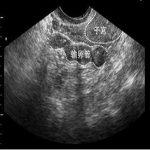

动态数字化子宫输卵管碘油造影(HSG)是最输卵管疾病诊断最精确的检查。安太拥有遥控数字化连续子宫输卵管碘油造影(HSG) 装置,动态数字化子宫输卵管碘油造影术是陈凤林教授发明的。它是通过导管将碘油持续连贯注入宫腔,患者和医生同时观看宫腔和输卵管动态影像,不但能知道子宫腔形态、输卵管是否通畅及阻塞的部位和程度,还能对轻度输卵管阻塞有疏通功效,所以它是不育症的必检项目。一次确诊率90%以上,输卵管阻塞单单经过造影后而怀孕者占27%。可以提供录像和电子图片,同时省去24小时拍片的程序。